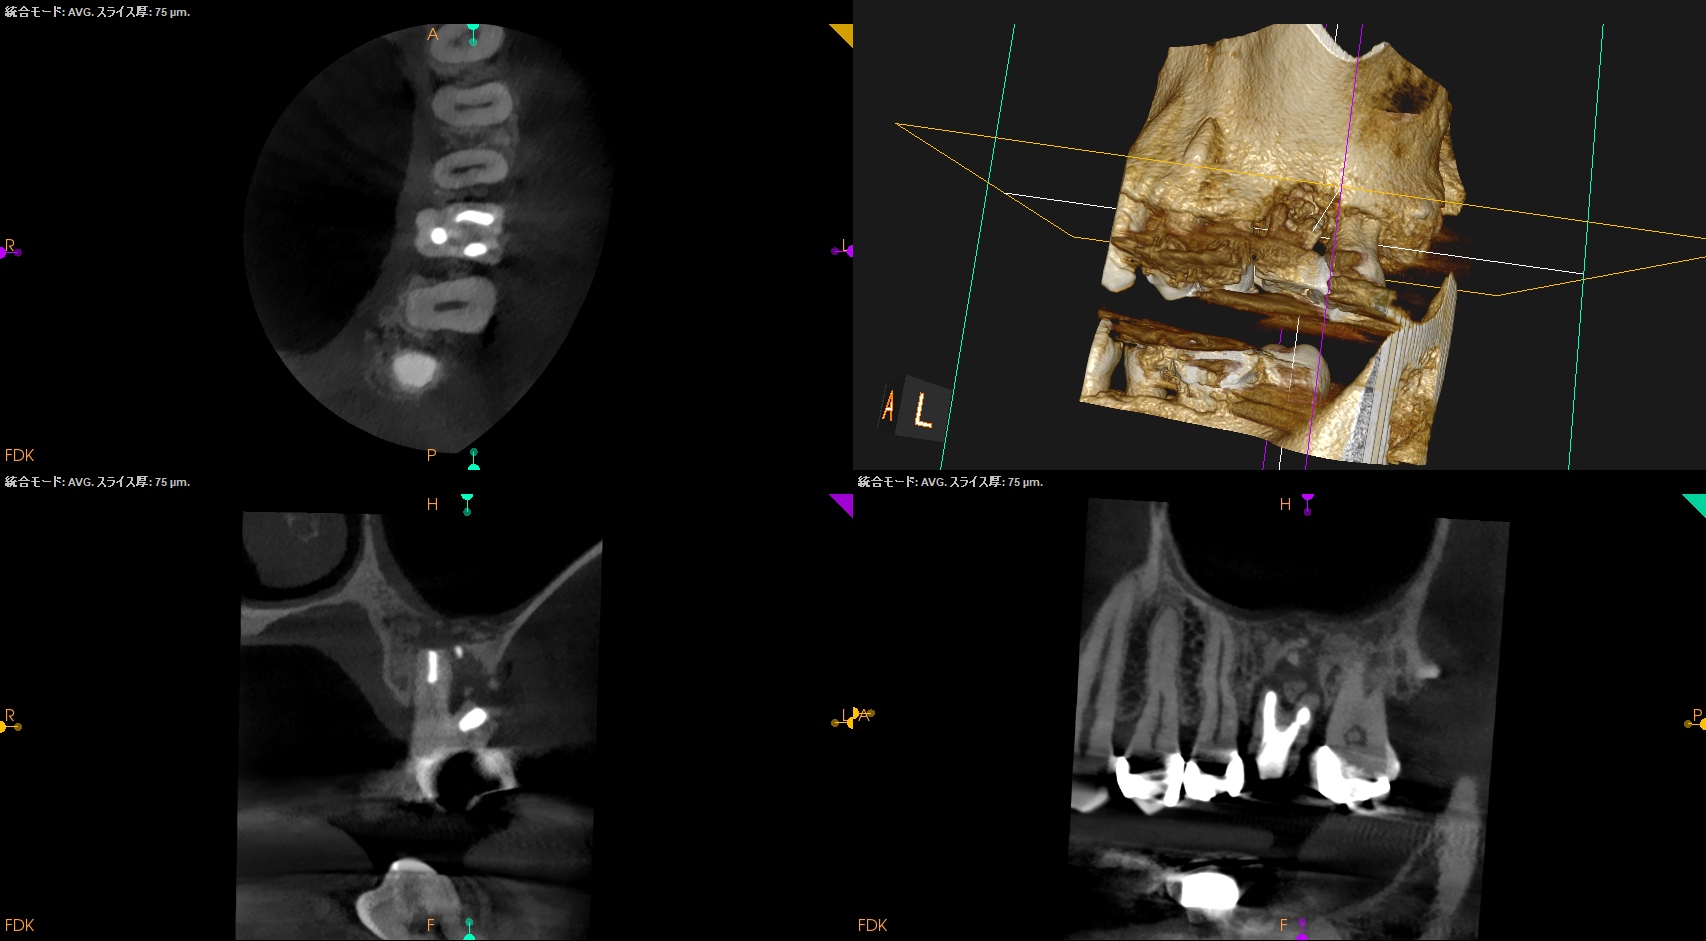

#14 Re-RCT 1yr recall(2024.6.10)

MB

DB

P

1年前よりも状況がひどくなる。

そこで、Apicoectomyを行うのだが、